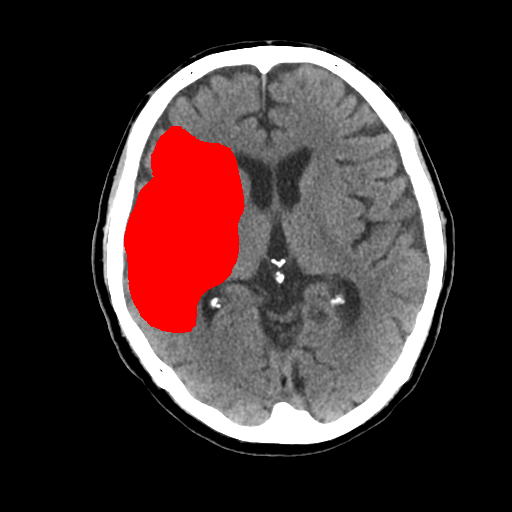

1-1. 高吸収領域の検出・表示例(下)

頭部CT検査において、周囲に比べ白く映る部分(高吸収領域)が見られる場合には、脳出血が疑われます。脳出血は高血圧・脳腫瘍・脳血管の異常などが要因となり、脳の動脈が破れて脳内部に出血した状態を指します。一方、周囲に比べ黒く映る部分(低吸収領域)が見られる場合には、脳梗塞が疑われます。脳梗塞は、脳内の血管が詰まるなどにより血液の流入が止まり、脳に酸素や栄養が行き渡らなくなる状態です。また、急性期の脳梗塞では、頭部CT検査において、灰白質と白質の境界が消失するなどの所見(ECS=early CT sign)が見られ(2)、こうした所見を見落とさずに治療につなげることが肝要です。